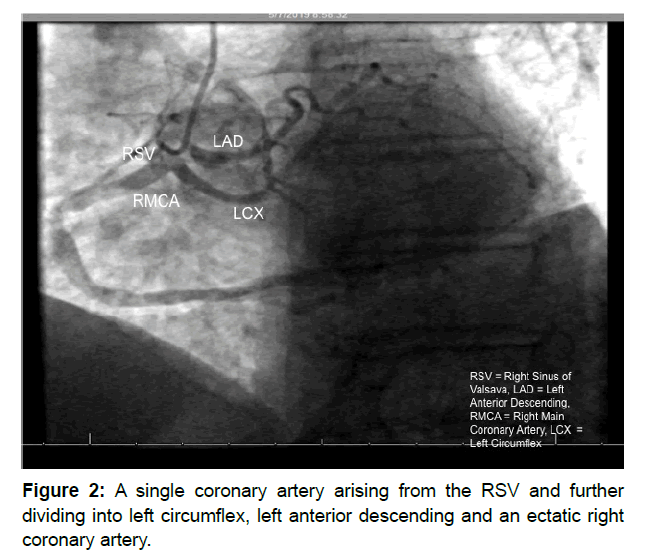

Our patient is an 82-year-old male with a past medical history of type 2 diabetes mellitus and hypertension with no history of cardiovascular events. In addition, he was a former smoker who had quit in 1980 but did have passive smoke exposure from working as a fireman. After undergoing a shoulder replacement procedure, he started to experience dyspnea and increased lower extremity edema. Transthoracic echocardiogram revealed normal systolic function with mild left ventricular hypertrophy and aortic stenosis. Following the initial visit, he then underwent a myocardial perfusion scan, which indicated decreased perfusion on inferior wall concerning for possible ischemia and an ejection fraction of 74%. Patient was then scheduled for combined left and right heart catherization. Angiographic imaging (Figure 2) revealed anomalous anatomy where the entire coronary system was derived from the RCA originating from the RSV. The RCA appeared to be a very ectatic vessel leading to disease-free posterolateral and posterior descending systems and a larger system of posterolateral LV extension branches. The first branch of the RCA was a Left Anterior Descending (LAD) that was patent proximally but showed high-grade stenosis of 95% in the mid-portion and further significant stenosis in the distal ends. The LAD also seems to have terminated prematurely before reaching the apex. The second branch of the RCA was a Left Circumflex (LCX) that seemed to have both a longer course and greater dilation than normal variant. The LCX also seems to have severe mid-stenosis of 80% but does give rise to three disease-free marginal branches. In addition, patient was noted to have elevated RA filing pressures with evidence for mild-to-moderately elevated pulmonary artery systolic hypertension. The patient tolerated the procedure well without complications. Subsequently, he followed up with a cardiothoracic surgeon for further evaluation, who recommended no need for further imaging including Coronary CT or surgical intervention, and continued surveillance monitoring. On further follow-up, lisinopril and furosemide were added to medication regimen, and strict glycemic control was recommended. Patient continues to be asymptomatic.